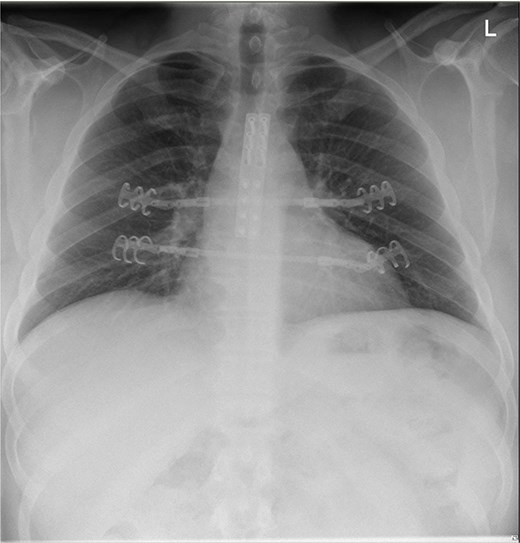

A 39-year-old male was admitted to our department after a severe crush with a forklift truck on his ribcage/thorax while at work. On arrival, he was conscious with stable vital signs (blood pressure 151/73, heart rate: 78 bpm, and saturation of 100% under 5 l) but complained of heavy right arm and chest pain. The clinical examination revealed an obese patient with a calculated BMI of 41 with a hematoma over the sternum and increased tenderness to palpation with no apparent instability. Deformity of the right arm with nerve damage in the radial territory was also noted. He had no previous medical history. The 3D computed tomography (CT) showed a type I MSD with osteochon dral dehiscence at the level of rib two bilaterally on the sternal side and ribs 4–6 left on the costal side with non-displaced bowing rib fracture of ribs seven and eight anteriorly on the left. An associated small pneumothorax, restricted pneumomediastinum, and the presence of a lung contusion posteriorly on both sides. No laceration, no pleural fluid (Fig. 1). The radiography of the arm showed a transverse, multi-fragmentary mid-diaphysis humeral fracture with bayonet position and significant angulation. The patient was first admitted to the intensive care unit (ICU) for surveillance; pain management was provided with a patient-controlled intravenous analgesia (PCIA) opioid pump, and 3-liter oxygen therapy was administered. The indication for reduction was primarily the severe displacement of the manubrio-sternal junction associated with the chondro-costal dehiscence. The overall stability of the fracture was challenging to assess due to the severe obesity, making a closed reduction even more difficult. Regarding the imagery, we assume that the thoracic cage’s overall stability would be insufficient. Secondly, the patient presented with persistent pain with the need for intravenous opioids. Finally, the patient had to undergo another operation for which the same general anesthesia could stabilize both fractures. After four days of scheduling, the patient underwent a chest wall reconstruction under general anesthesia associated with a patient-controlled epidural analgesia (PCEA). The patient was installed in a supine position with arms abducted. A 15 cm bi-submammary incision up to the sternal fork was realized. Dissection until manubriosternal dislocation was retrieved, reduction was obtained with two 8-hole locking compression plates and secured with 16- and 18-mm screws. Since the chondro-sternal fracture was not eligible between the cartilage and bone for direct osteosynthesis, we performed a fixation at the level of ribs 4–5 bilaterally using titanium rib clip plates stabilized between them by a titanium connecting bar. An open reduction with internal fixation treated the humeral fracture with 4,5 mm 10-hole plates. The patient was extubated directly after the procedure and received postoperative physical and respiratory therapy. He was discharged on postoperative day 4. After two months, the patient still presents limited mobilization on his right hand but has evolved favorably on the thoracic sides with no signs of sternal instability. His radiography showed a correct alignment of the manubriosternal joint (Fig. 2).